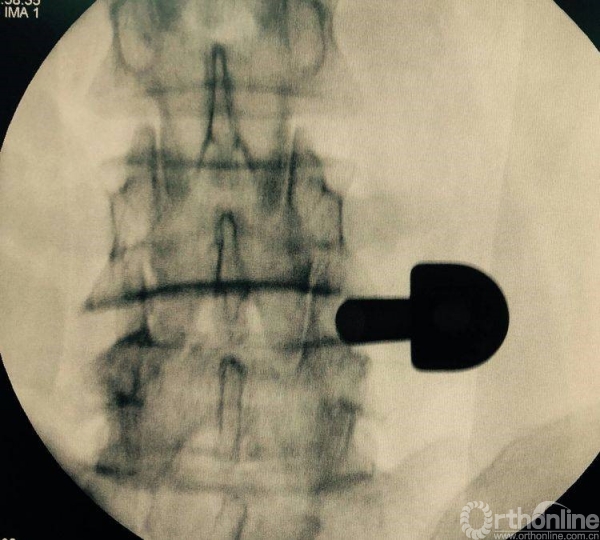

处理干净椎间隙后,透视观察工作通道的位置,镜下看到前纵韧带的纤维交错位置,为减压充分标志

正位观察透视,判断是否处理至边缘

12号试模决定融合器大小

充分植骨(关节成型时的自体骨质、也可配合异体骨使用),然后植入融合器,镜下观察融合器和硬膜囊位置并透视再次确认

正侧位透视观察滑脱是否复位、融合器及植骨的位置